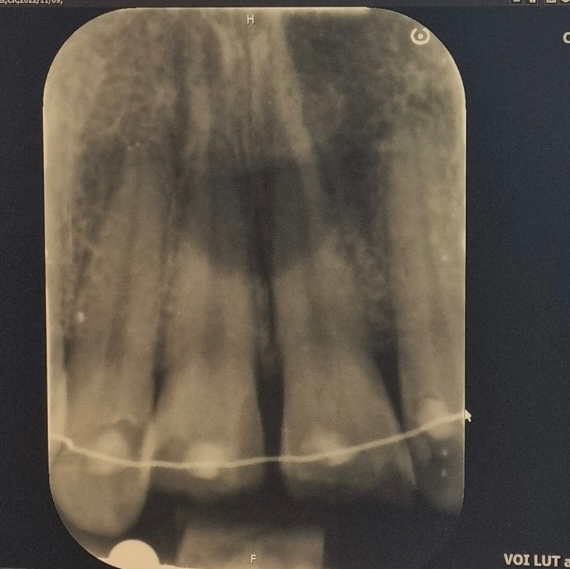

사진에서 보시다시피(이안쪽에 교정 유지장치 있었습니다)

수요일 점심쯤 바로 대학병원에서 신경치료를 했습니다..(다끝낸건 아니고 다음번에 마무리 할듯 합니다.. )

오늘(일)이 사고 및 신경치료일(수)로부터 약 3일정도 되는 날인데 부러진이 와 주변 이 쪽에 뭐라도 닿으면 좀 시린(?)느낌이 드는데 원래 이러나요?

만약에 주변 조직에 대해서 나타난 증상이라면 2주 정도 시간이 지나면 사라지지만 현재 외상된 정도를 보았을 때는 상아질 손상이 있을 수 있으며 시간이 지나도 나아지지 않으면 신경치료를 해야할 것으로 보입니다. 즉 현재로서는 신경까지 손상되어 나타나고 있을 수 있으므로 조금 더 경과를 지켜보아야 합니다.

치아자체는 신경이 없어서 괜찮겟지만 그주위 조직들이 말씀대로 충격을 받앗기 때문에 시린증상이 나타날수 있습니다. 정확한 날짜는 알수 없지만, 짧게는 몇주 길게는 몇달까지도 증상이 나타날수도 있습니다.

약 한달정도는 통증이 지속될 수 있으며 주위 다른 치아들도 신경에 문제가 생길 수 있으므로 주기적으로 관찰하는 것이 좋겠습니다